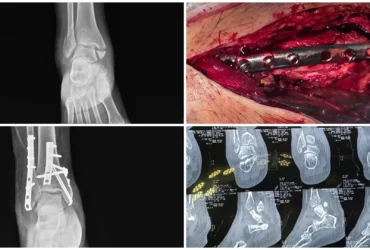

Masquelet Technique & Ilizarov for Distal Tibia Bone Defect | Balanku Hospital

We Provide Orthopedic Service by Experience Doctors

We has a dedicated multidisciplinary team that cares for and surgically repairs acute fractures for patients of all ages. We offer expertise in fractures of the hip, arm, leg, hand, foot and ankle.